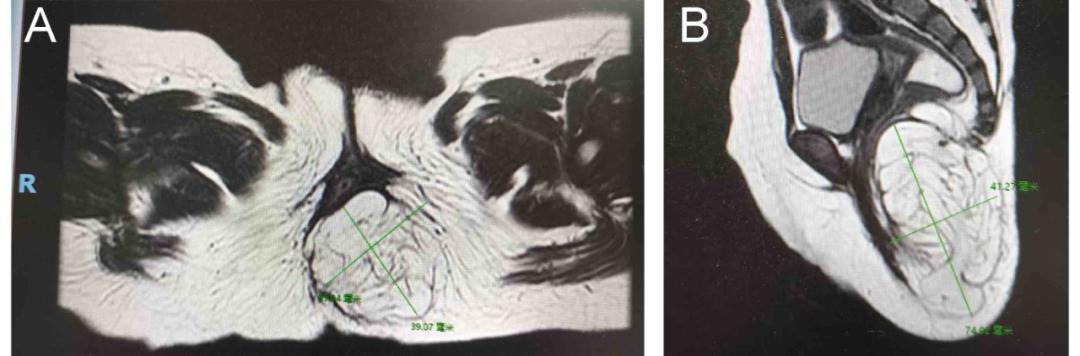

一家人觉得不对劲,然后带小编去当地医院看病,骨盆MR检查提示 “左屁股脂肪瘤”。“肿瘤”这个词让父母惊慌失措。经询问,小编一家来到中山市第六医院儿童手术,寻求进一步治疗。科室主任王德娟主任医生接诊,建议小编先完善相关检查。

王德娟担心肿瘤与腰椎神经有隐藏的关系,因为骶尾部肿块与直肠肛门、马尾神经和尾骨相邻,并伴有排便困难等临床表现。如果影响腰椎,会造成全身不良后果,严重者可能瘫痪。

经过慎重考虑,王德娟团队结合胃肠外科、麻醉科、儿科、放射科、神经外科等专家,结合医院影像检查结果,对花花的病情进行了全面评估,消除了肿块与骶尾神经的联系,决定通过臀部微创手术切除肿块。